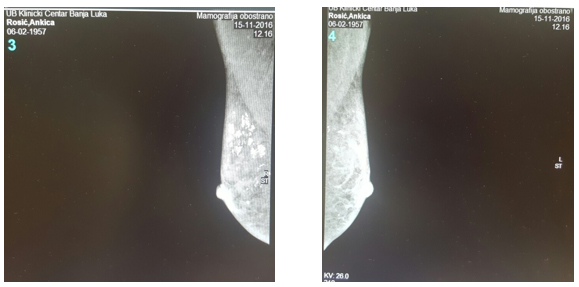

Slika 3. i 4. Nativna mamografija obe dojke i aksilarne regije: Prepektoralno obostrano, izraženije u desnoj dojci se uočavaju multiple intraduktalne segmentne kalcifikacije koje u potpunosti ispunjavaju duktuse. Između ovih amorfnih kalcifikacija se uočavaju multiple pojedinačne mikrokalcifikacije suspektno malignih karakteristika